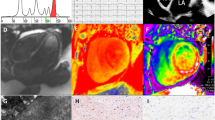

In order to study the complex relationship between systolic and diastolic function in CA, a research group [42] compared the mean strain values in a group of patients with systemic amyloidosis without cardiac involvement (NCA) with a control group. The investigators demonstrated that in NCA the strain values were lower than the control group. Therefore, they showed that is not possible to exclude a systolic impairment even in patients with no evidence of cardiac involvement. In fact, the previous belief, according to which systolic dysfunction occurs only in the advanced stage of CA, is based on studies that do not consider the myocardial longitudinal function. The latter is given by the motion of the subendocardial fibers. To support this, Vogelsberg et al. [13••] found a distinct pattern of myocardial late gadolinium enhancement (LGE) in the group with biopsy-proven cardiac amyloidosis. Most of these patients had LGE distributed over the entire subendocardial circumference, where there are the fibers responsible of the myocardial longitudinal function (Fig. 2).

Longitudinal, circumferential, and radial strain in the different stages of CA. (From Di Bella et al. Eur Heart J Cardiovasc Imaging. 2014 Dec;15(12):1307–15, by permission of Oxford University Press) [24••]